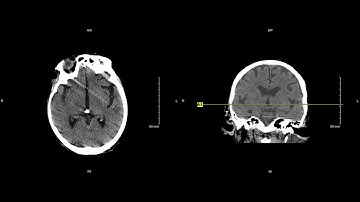

Unremarkable Non-Contrast CT Axial Bone Window-Example 3